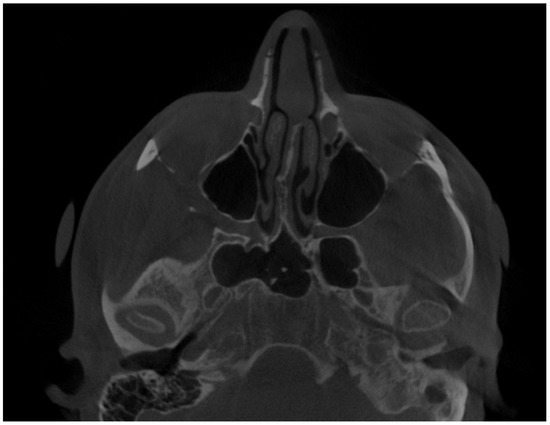

Figure 2.

CBCT axial view—enlargement of the left mandibular condylar head. Atypical osteophytes or bone irregularities can have different shapes and sizes while the condylar head is evaluated. The condylar head might have a different shape, size, and contour compared to the opposite healthy side.